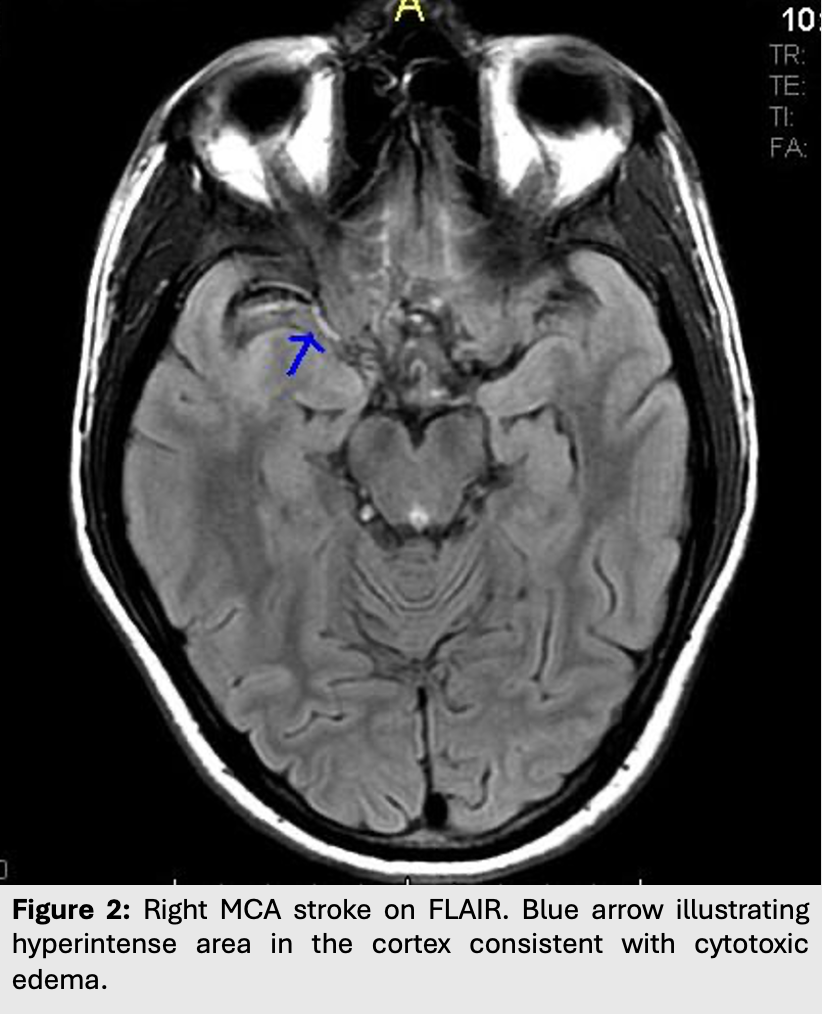

This leads to edema with restriction of water diffusion. As such, cytotoxic edema will appear hyperintense on both T2/FLAIR and on DWI.

This type of edema is most commonly seen in strokes or ischemic syndromes.

Figure 2: Right MCA stroke on FLAIR. Blue arrow illustrating hyperintense area in the cortex consistent with cytotoxic edema.